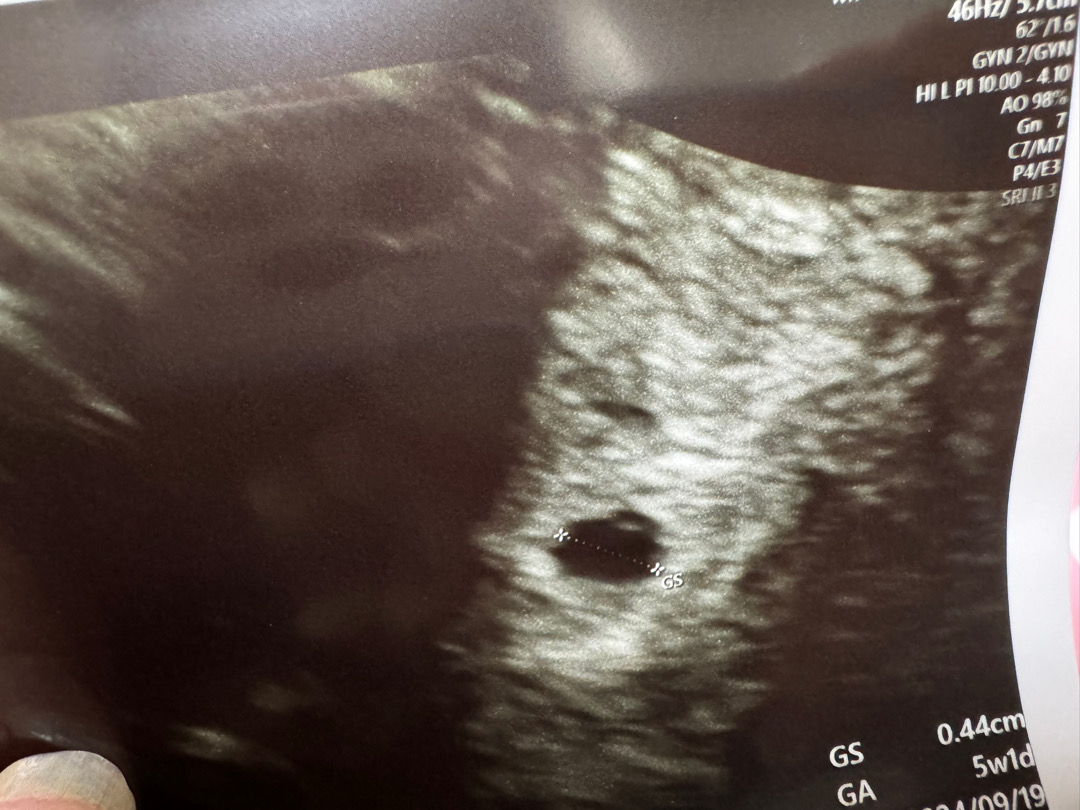

난황이 보이나요?

10년 전 첫번째 인공유산 21년 두번째 23년 세번째 계류유산 24년 너무나 감사하게 아이가 찾아왔어요 ㅠㅠ 이번엔 끝까지 지켜보고자 노력을 … 사진에 난황이 보이나요?! 불안한 나날을 보내고 있어요 ㅠ

지금 만들어지는거 아닐까요 ? 저도 비슷한 상탠데 선생님이 배란니 늦게되서 그런가 아기집은 지금 주수에 비해 작지만 난황은 지금 만들어지는거 같다 하셨거든요 ㅎㅎ